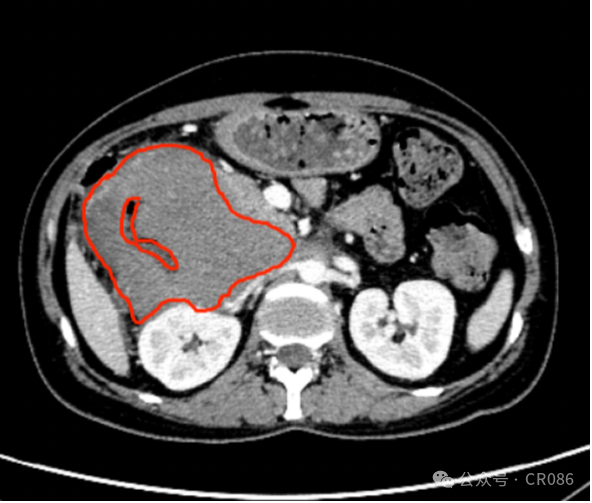

11月,袁姐住进了病房,做了CT检查,肿瘤最大横截面大小:9.9*9.5cm。妥妥一个“小柚子”,这么巨大的肿瘤真是不由让人倒吸一口凉气,难怪医生已经放弃努力。

3.png

2024.11.06 红色圈出部分为肿瘤。